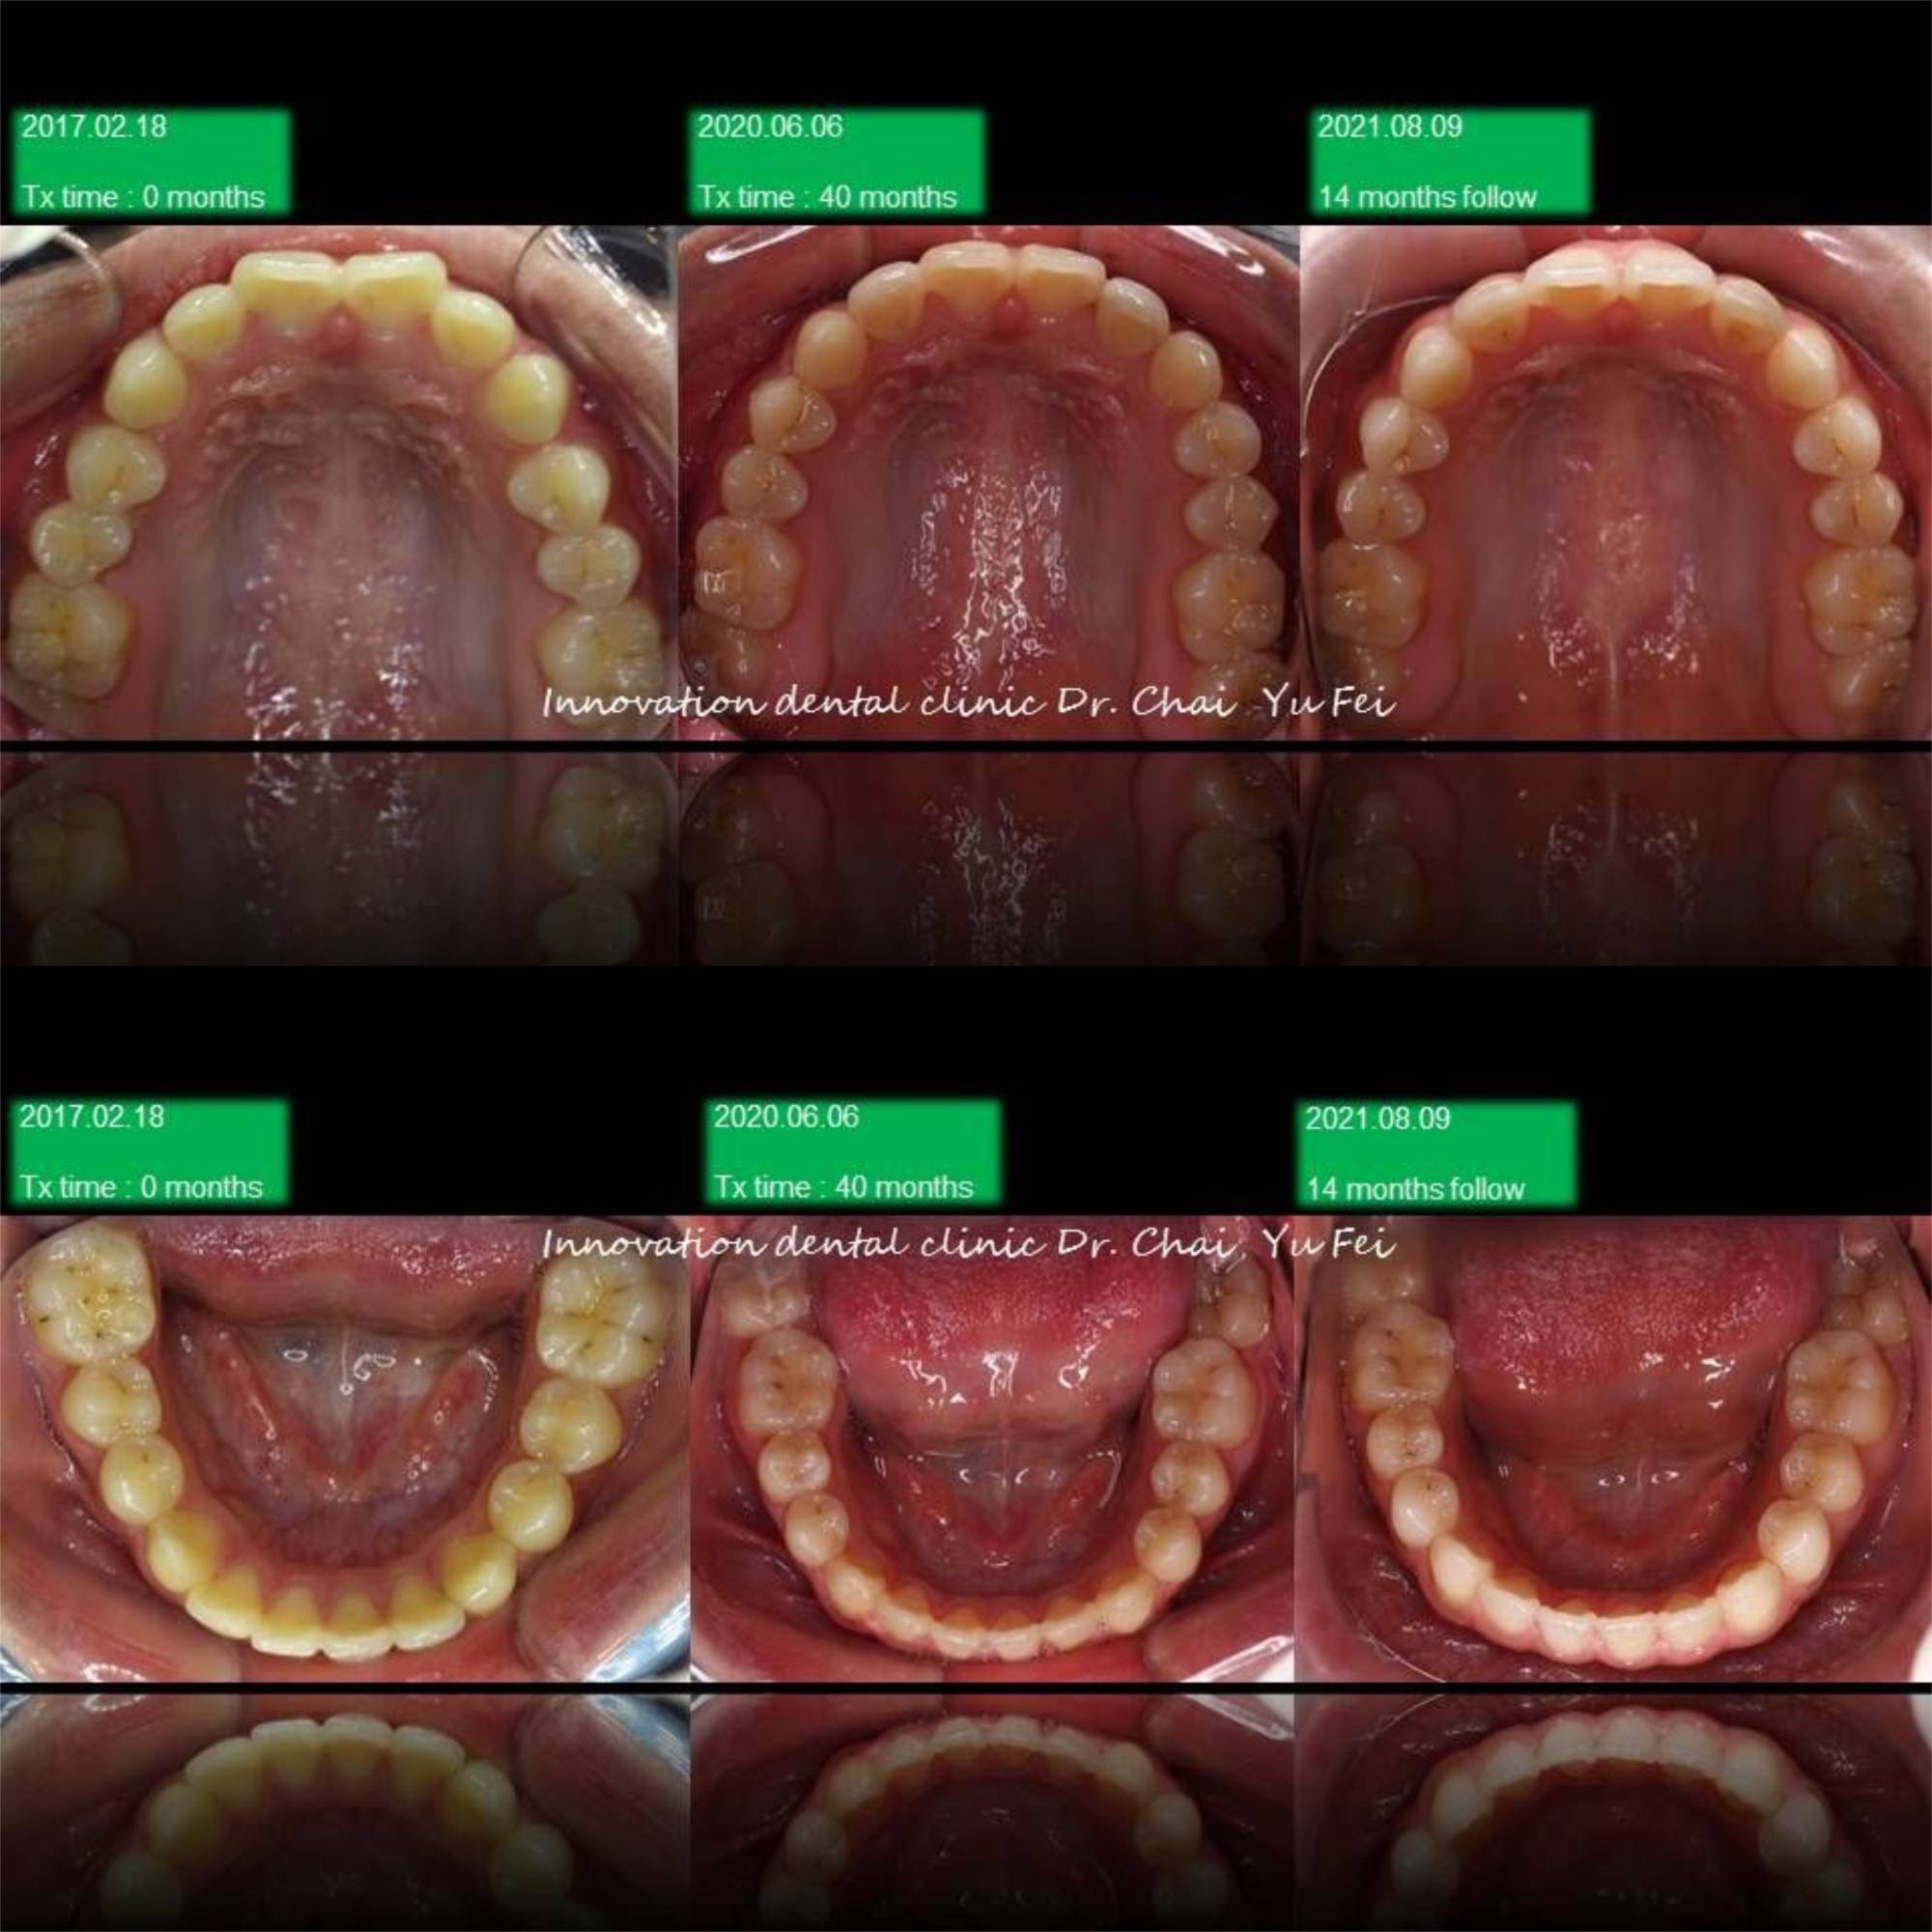

[ 治療方式 ] : 利用矯正 , 將前突的齒列內收,改善外觀,右側咬合高度喪失重建,植牙,恢復美觀功能

[ 治療時間 ] : 40 個月

男生的發育都是很長遠的,看到初始這樣的暴牙可能會擔心需要拔牙改善,但是考量孩子的年紀與生長潛力

我們採用上顎到後期用骨釘加一層保險去控制,下顎讓孩子自然生長的方式,現在這位高材生都已經升大學了

Non-extraction case .

Upper control by mini screw , lower let him grow automatically

很感謝他矯正期間的配合,很有耐心地讓我在最後改中線的部分花了不少時間。